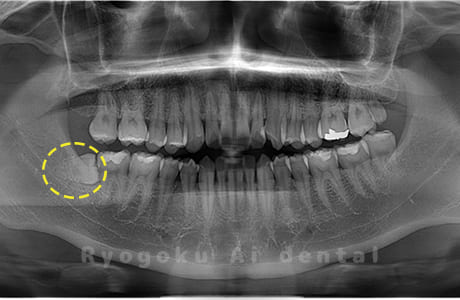

Case09

- 下顎左の水平埋伏智歯

- 下顎左の水平埋伏智歯を抜歯したケースです。

<リスク・副作用>

手術後は痛み、腫れ、痺れなどの副作用が生じる場合があります。